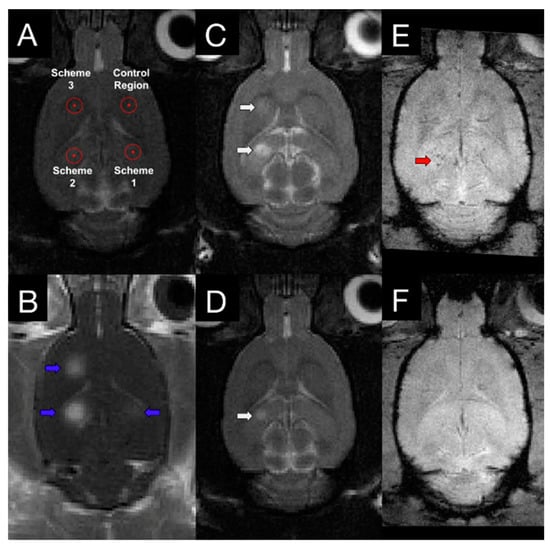

- Liu, H.-L.; Hsu, P.-H.; Chu, P.-C.; Wai, Y.-Y.; Chen, J.-C.; Shen, C.-R.; Yen, T.-C.; Wang, J.-J. Magnetic resonance imaging enhanced by superparamagnetic iron oxide particles: Usefulness for distinguishing between focused ultrasound-induced blood-brain barrier disruption and brain hemorrhage. J. Magn. Reson. Imaging 2009, 29, 31–38. [Google Scholar] [CrossRef]

- Liu, H.-L.; Wai, Y.-Y.; Chen, W.-S.; Chen, J.-C.; Hsu, P.-H.; Wu, X.-Y.; Huang, W.-C.; Yen, T.-C.; Wang, J.-J. Hemorrhage detection during focused-ultrasound induced blood-brain-barrier opening by using susceptibility-weighted magnetic resonance imaging. Ultrasound Med. Biol. 2008, 34, 598–606. [Google Scholar] [CrossRef]